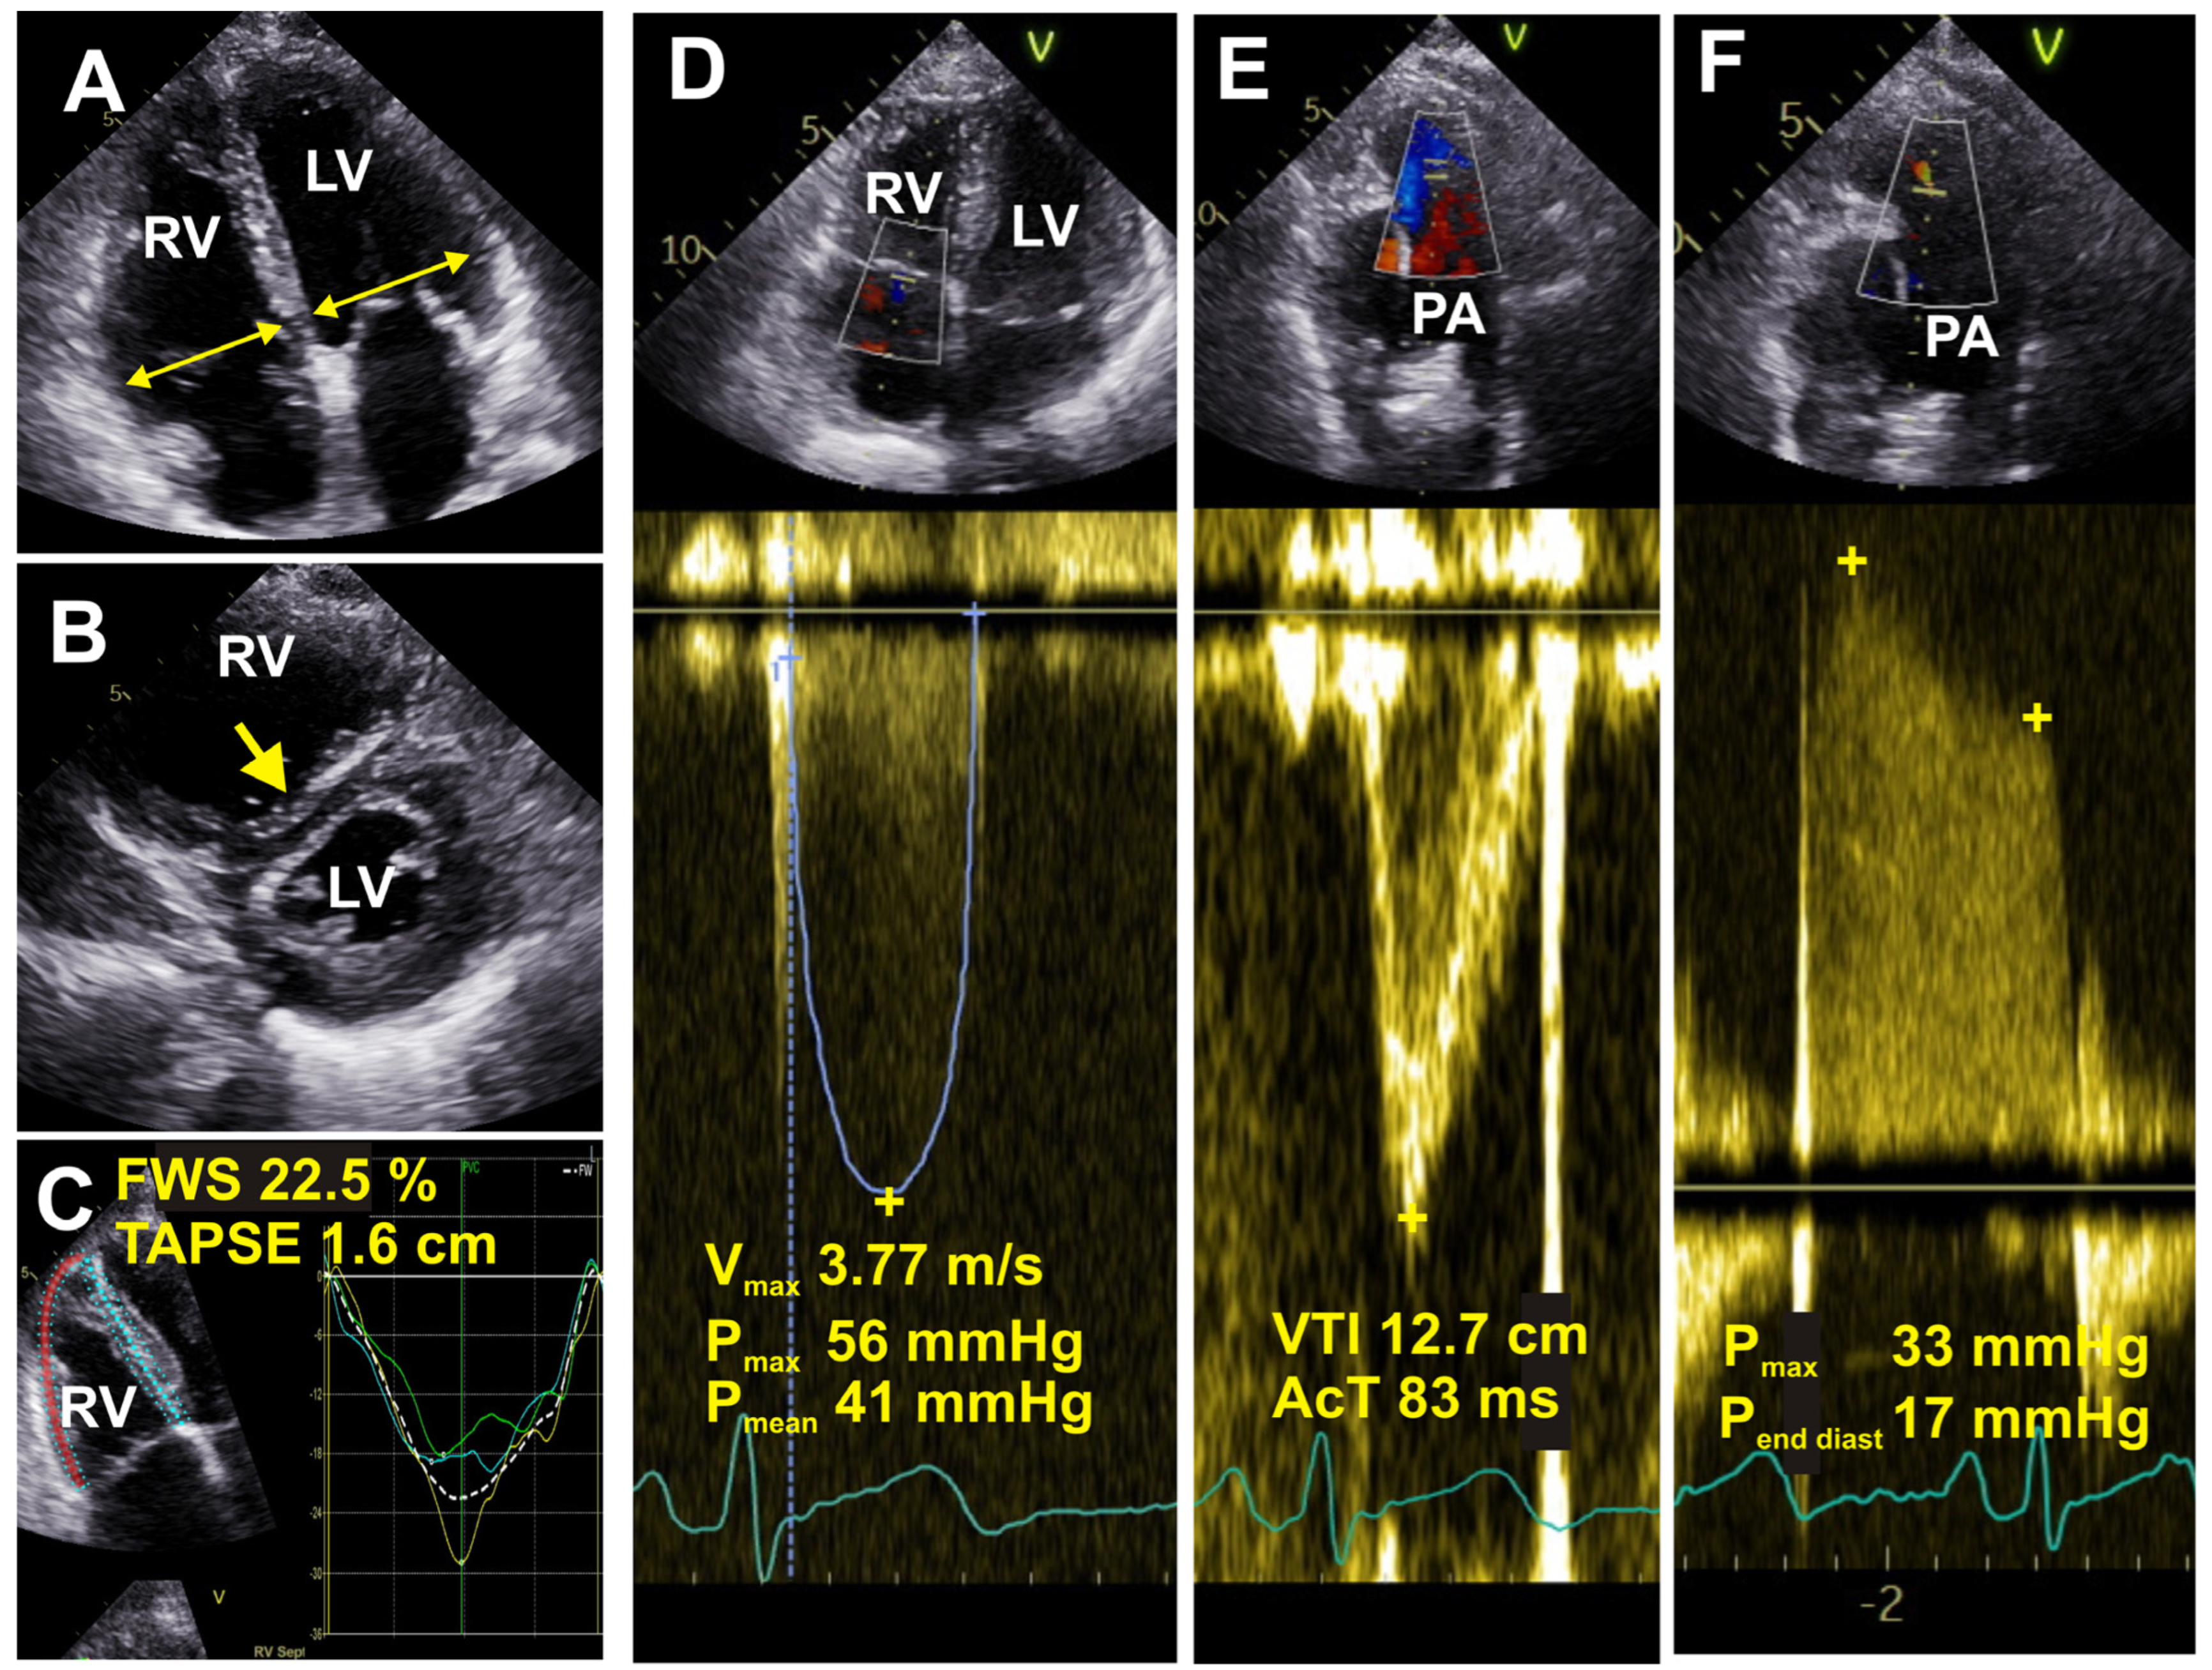

Echocardiography is probably the most widely used non-invasive diagnostic tool for assessing PH (Figure 2). It provides high spatial resolution and adequate morphological, functional, and hemodynamic analysis. However, the information obtained from echocardiography can only grade the probability of PH rather than delivering a conclusive diagnosis.

Figure 2.

Echocardiographic images are shown in a patient with idiopathic pulmonary fibrosis. (A) Four chamber view: the maximum diameters of the right (RV) and left (LV) ventricles are measured (yellow arrows). Dilated RV with a ratio to left ventricle at about 1.0 is shown. (B) Parasternal short-axis view: large RV, flattened intraventricular septum (yellow arrow). (C) Right ventricular speckle strain, four chambers adjusted for RV: tricuspid annular plane systolic excursion (TAPSE) is reduced at 1.6 cm, and free wall right ventricular strain (FWS) is also reduced at 22.5%. (D) Four chamber view: septal deviation towards LV showing evidence of elevated RV pressure. Continuous wave Doppler through the tricuspid valve and Vmax is elevated at 3.77 m/s. (E) Pulse wave Doppler through right ventricular outflow tract (RVOT) indicating shortened pulmonary artery (PA) acceleration time (AcT) at 83 ms. (F) Continuous wave Doppler: PA regurgitation, estimated end diastolic PA pressure is elevated at 17 mmHg.